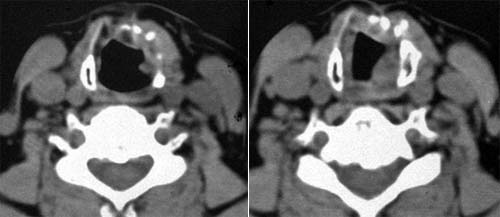

Рис. 3. Компьютерная томограмма больной с посттравматичекой рубцовой деформацией гортани.